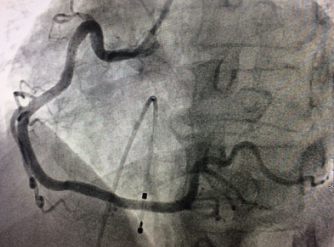

??? 近日,在我院心血管內(nèi)科病房內(nèi),70歲的患者張大爺康復(fù)出院,患者及家屬握著醫(yī)生的手連聲道謝。誰能想到,這樣一個(gè)思維清晰、開朗健談的老人,10多天前還因?yàn)榧毙許T段抬高型心梗(急性心肌梗塞的一種)瀕臨死亡,在心臟導(dǎo)管室內(nèi)進(jìn)行爭分奪秒的搶救呢!?突發(fā)胸痛3小時(shí) ??70歲老人病情危急????家住江...